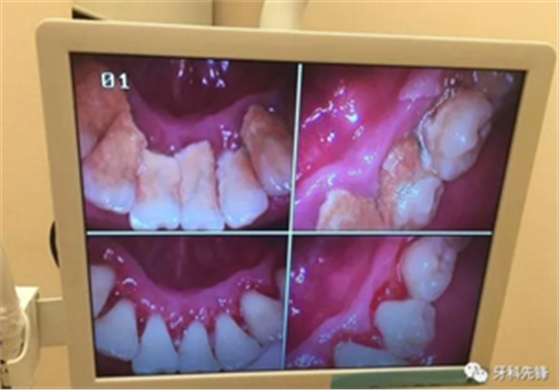

臨床上確實存在這樣的情況,但是作口腔醫(yī)生,我為一名可以負責(zé)任的告訴大家,如果不清除掉牙結(jié)石后果會更加嚴重,甚至有脫落的風(fēng)險。原理是什么呢?因為牙結(jié)石、牙菌斑的破壞能力是極其強大的,只要它存在就會一直不斷的刺激壓迫牙齦,時間久了則會導(dǎo)致牙齦紅腫出血、牙槽骨吸收、牙齦萎縮、牙齒松動甚至脫落等情況,這是一個緩慢發(fā)展的病變過程,單純的靠牙結(jié)石撐住牙齒不讓其出現(xiàn)病理性移動從根本上講是極其不現(xiàn)實的,有點兒“掩耳盜鈴”的意味,不僅撐不住反而會加快牙齒松動、脫落。很可怕吧,尤其是對于我們成年人來說,現(xiàn)有且僅有的一副恒牙竟然還被牙結(jié)石牙菌斑禍害成這個樣子,應(yīng)該算是一種不幸吧!